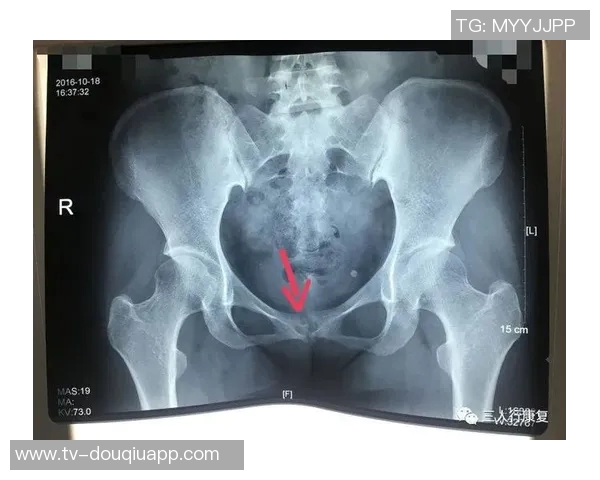

1、耻骨炎的基本概念与症状

耻骨炎是一种常见于运动员中的损伤,尤其是在进行高强度训练或比赛时更为普遍。它主要表现为耻骨区域的疼痛和不适,通常伴随着活动能力下降。在运动中,特别是涉及到快速变向、高强度跑动等动作时,疼痛感会更加明显,这使得许多运动员无法正常发挥。

此外,耻骨炎还可能导致局部肿胀和压痛,使得患者在日常生活中也遭遇困扰。这种疼痛不仅限于身体运动,还可能延伸至心理方面,例如焦虑和沮丧,因为持续的不适感限制了他们参与喜爱的体育活动。